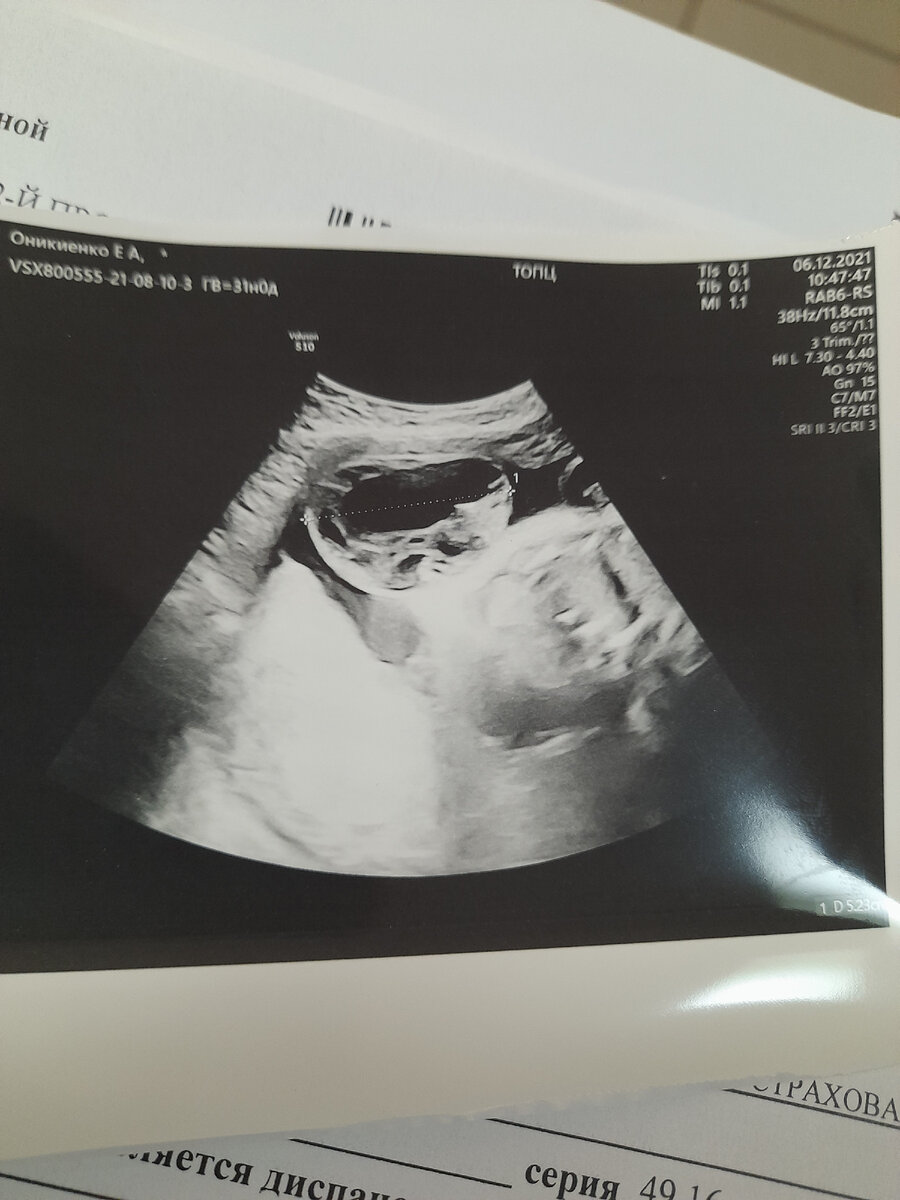

Р.S. на черно-белом узи видно саму грыжу